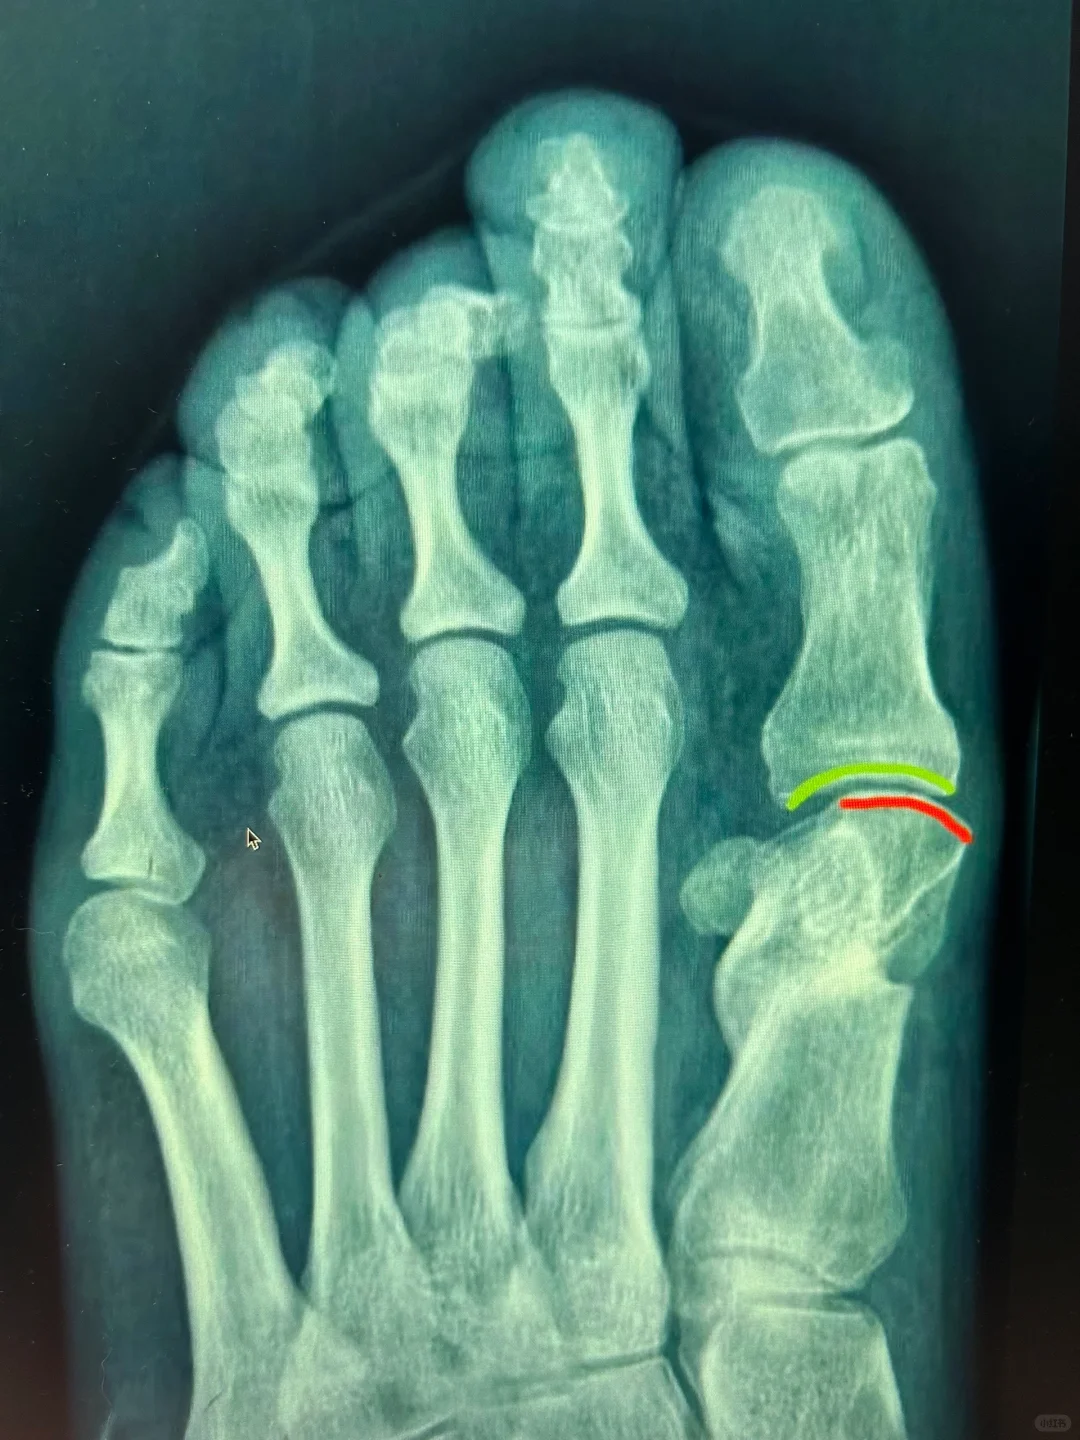

拇外翻术后硌脚原因分析